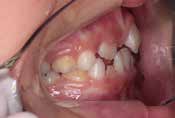

鼻がつまりやすく、口呼吸をしているために上あごが狭い状態でした。また上の前歯がかなり前へ傾いているため、お口をきちんと閉じていることができません。さらに、下の前歯もでこぼこしていました。

治療を終えて

装置によって上あごを拡大し、下あごを少し前へ成長させたことで、永久歯がきれいに並ぶスペースを確保しました。また、お口の機能が向上したことから鼻がよく通るようになり、口呼吸も改善され口も閉じやすくなったので顔の表情もよくなりました。

主訴・治療内容 下あごが後ろに下がり、出っ歯のようになっていることを心配して、無料相談に来院されました。